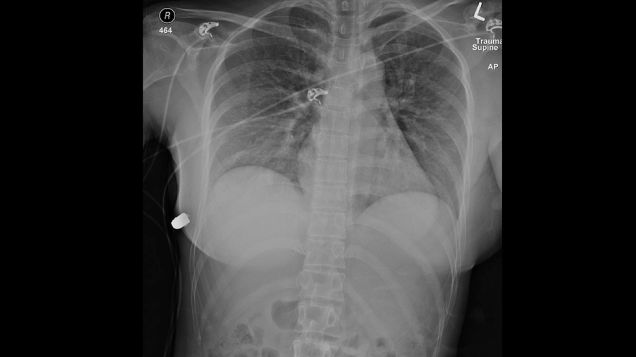

Doctors say a woman’s silicone breast implants deflected what could have been a fatal bullet, stopping it from reaching her heart. Amazingly, this is not the first time such a thing has been reported in the medical literature.

Source: Gizmodo – A Woman’s Breast Implants Saved Her Life From a Gunshot, Doctors Say